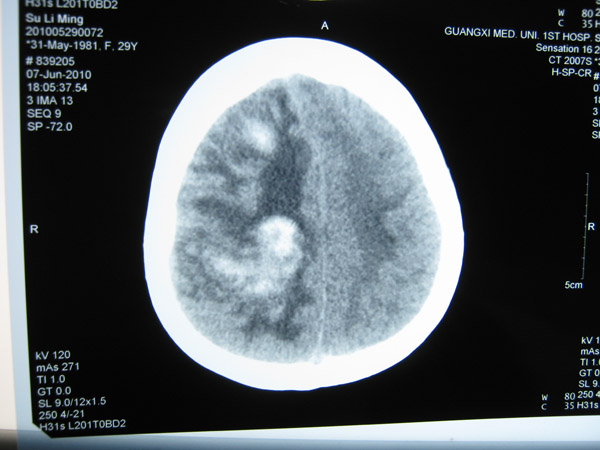

2011年5月1日,覃某顺产1名女婴后出现发作性意识障碍,伴双目上视,伴牙关紧闭、口吐白沫、四肢抽搐、二便失禁,醒后伴头晕、四肢乏力、左侧肢体麻木等不适症状,遂到当地医院就诊。在其住院过程中出现意识障碍伴左侧肢体活动障碍、左下肢肿胀等症状,在进行头颅MRI+MRA等检查后,覃某被当地医院诊断为“颅内静脉窦血栓形成并伴脑皮质出血、症状性癫痫、左下肢静脉血栓形成”。

头颅CT1